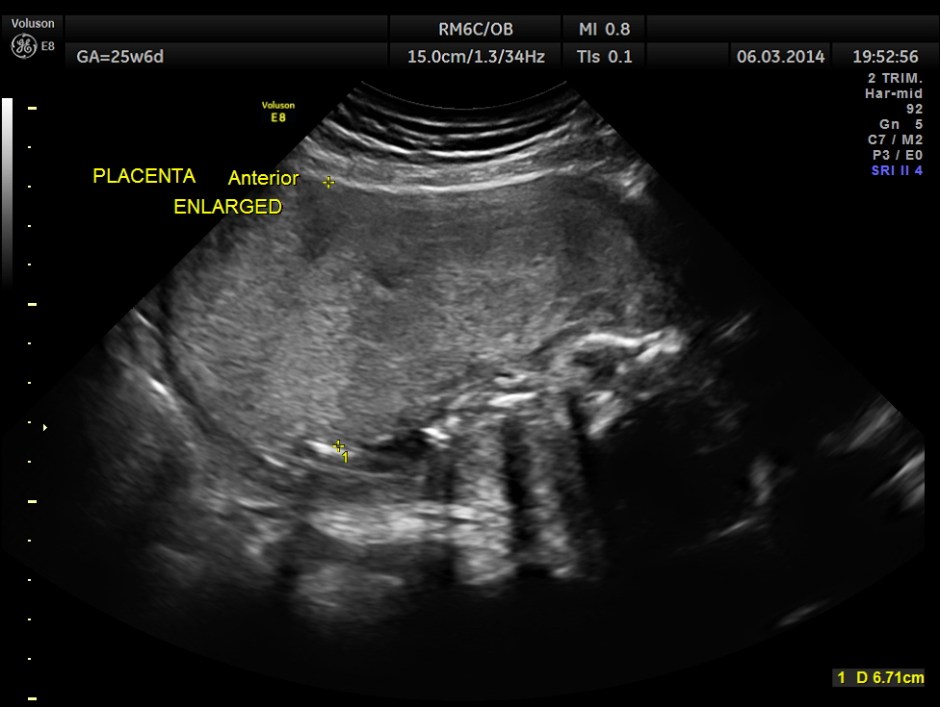

The following report is of the same patient after 5 weeks 3 days.

The GA was around 25 weeks , but the AUA was around 19 to 20 weeks. All parameters – BPD, HC, AC, FL are < 2.3 %tile and all other long bones are < 5.0 %tile.

Prominent placentomegaly seen .